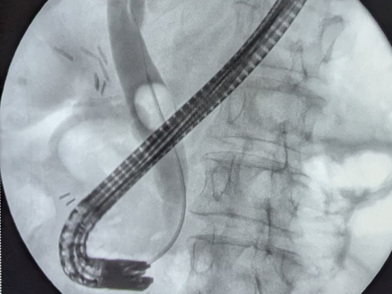

Основной особенностью, внедрённой в широкую клиническую практику методики, является одномоментное сочетанное использованием двух миниинвазивных технологий. Операции выполняются при помощи специального оборудования через небольшие проколы передней брюшной стенки и через ротовую полость пациентов.